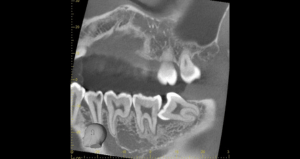

右下の親知らずが疼く症例

- 抜歯前写真(レントゲン)

- 抜去歯の写真(CT画像)

| 年齢 | 30代・女性 |

|---|---|

| 主訴 | 右下親知らずが疼く |

| 親知らずの生え方 | 横向きに生えている |

| 抜歯時間 | 40分 |

| 費用 | 約8,000円(保険診療、CT代含む) |

| 抜歯内容 | 右下の親知らずは横向きに生えて埋まっているため、麻酔をし親知らずの奥に切開を入れて歯ぐきを開き、歯を囲んでいる骨を削り歯の頭部分を割って出してから、残った根の部分を取り出して抜歯は終了しました。 歯ぐきを切った部分は糸で縫っています。このケースでは根の先端が神経に近く麻痺のリスクがありましたが事前にCTを撮影し、神経との位置関係を確認していたため、麻痺が残ることはありませんでした。 約1週間後に糸取りを行い、その際も多少の痛みや腫れはありましたが後日その痛みも無くなりました。 |